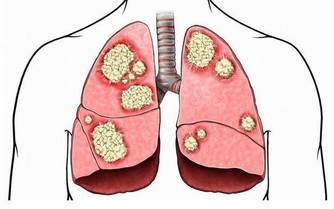

這裡說的“它”呢,其實就是生活中非常常見的胡蘿蔔。胡蘿蔔又稱為紅蘿蔔,含有豐富的醣類,脂肪,胡蘿蔔素,花青素,纖維素,各種維生素(VA、VB),鈣、鐵、磷,鎂,鉀等礦物質。中醫認為其性平味甘,歸脾、肺經,具有健脾消食、行氣化滯、潤腸通便、壯陽補腎、通氣止咳、益肝明目之功效。非常適合糖尿病、高血壓、皮膚粗糙、食慾不佳、腸胃不適、便秘、營養不良、夜盲症、乾眼症、性能低下、百日咳等患者食用。